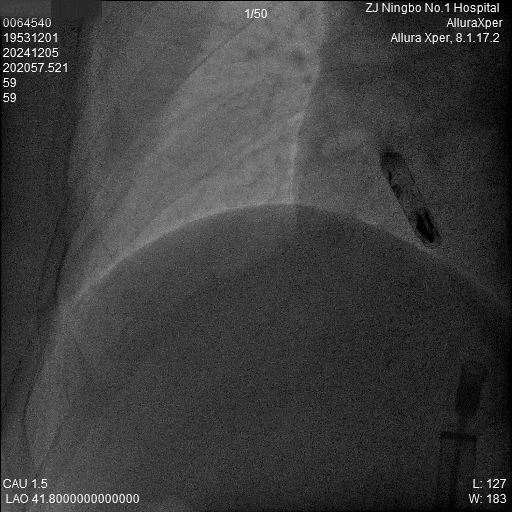

3.调弯进入右室低位间隔后造影,位置理想。左前造影明确贴靠间隔。

a)RAO